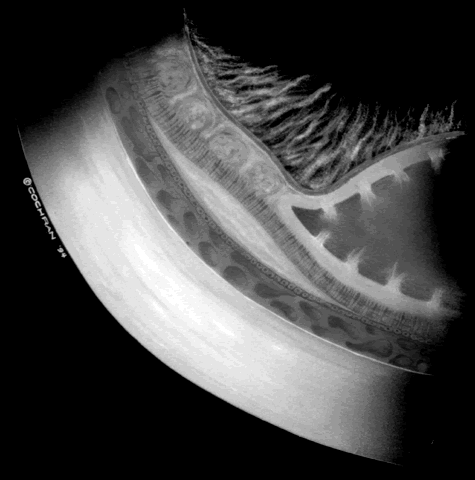

ROP accounts for a large number of retinal detachments in the pediatric population. The International Classification of Retinopathy of Prematurity helped greatly to improve communication about, and consequently treatment of, ROP. It describes affected eyes in terms of stage, zone, and absence or presence of plus disease18 (Figs. 1, 2, and 3). Screening of premature infants is an important feature in the care of ROP, which is perhaps the most significant and enduring finding of the Cryotherapy for Retinopathy of Prematurity Study (Cryo-ROP Study).19

Fig. 1. Stages of retinopathy of prematurity. A. Stage 1, showing a small white line visible between the avascular and vascularized retina. B. Stage 2, with the junction showing a wider white line between avascular and vascularized retina. C. Stage 3, with frank neovascularization extending into the vitreous cavity from the area posterior to the retinal ridge. D. Stage 4A, showing peripheral retinal detachment with the macula attached. E. Stage 4B, with a partial retinal detachment with the macula detached. F. Stage 5, showing total retinal detachment.